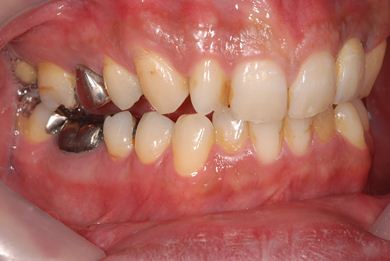

インプラントの症例写真 IMPLANT

抜歯即日スピードインプラント治療

| 性別/年齢 | 男性 / 36歳 | ||||||||||||||||||||||||||||||||

| 主訴 | 前歯が折れていてないので、インプラント治療を希望。 | ||||||||||||||||||||||||||||||||

| 治療内容 | インプラント1本(抜歯即日スピードインプラント)、ハイブリッドセラミッククラウン1本 | ||||||||||||||||||||||||||||||||

| 総治療費 | 257,250円 | ||||||||||||||||||||||||||||||||

| 治療期間 | 7ヶ月 |